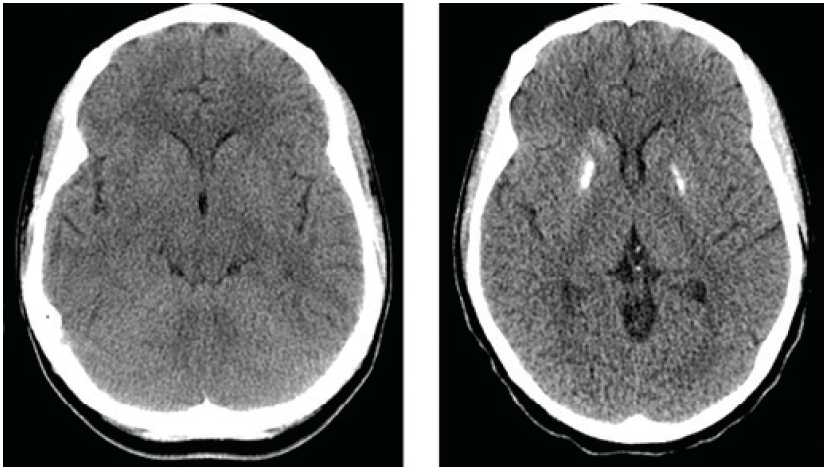

Sharla Rent, MD; Katherine Forrester, MD; Marta King, MD

A 19-year-old African American young adult with systemic lupus erythematosus presented to the emergency department with acute agitation and altered mental status.